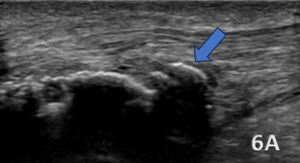

HAGLUND’S DEFORMITY

Figure 6A (LAX View):

A Haglund’s deformity is shown as cortical irregularities and a bony prominence on the posterior aspect of the calcaneus near the Achilles tendon insertion. The overlying soft tissues, including the retrocalcaneal bursa can show signs of inflammation, appearing hypoechoic or swollen. The Achilles tendon itself demonstrates thickening and increased echogenicity at its insertion due to chronic irritation. Additionally, there may be evidence of bursitis, with fluid accumulation seen as an anechoic or hypoechoic area within the retrocalcaneal bursa.